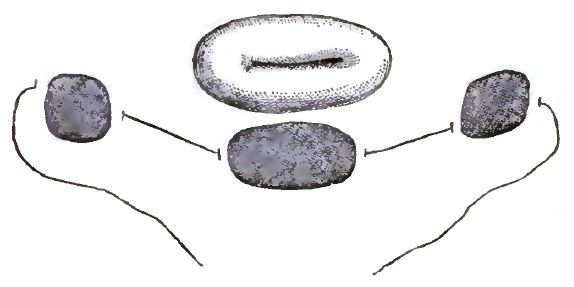

| 19. | SCHULTZE'S SLEIGH PESSARY IN PLACE |